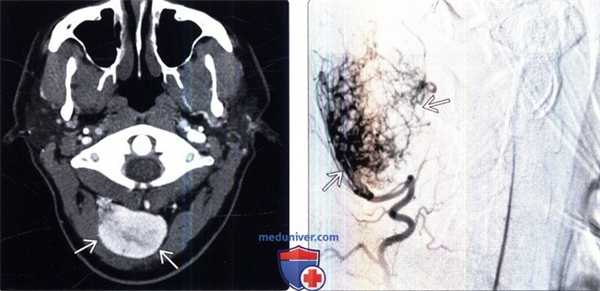

При тотальной селективной каротидной ангиографии (КАГ) выявлено гиперваскуляризированное образование передней и средней черепной ямок слева, размером 7×7 см, питающееся ветвями левых средней мозговой артерии (СМА), наружной сонной артерии (НСА), интракраниального сегмента внутренней сонной артерии (ВСА). Венозные синусы проходимы, без признаков тромбоза (рис. 1).

Рисунок 1. Селективная КАГ(S). Гиперваскуляризированное образование передней и средней черепной ямок слева, размером 7×7 см, питающееся ветвями левых СМА, НСА, интракраниального сегмента ВСА. Венозные синусы проходимы, без признаков тромбоза.

При КТ головного мозга преимущественно в левой лобно-височно-теменной области определяется крупное объемное образование с достаточно четкими бугристыми контурами размером 78×76×64 мм, в базальных отделах прорастающее в правую лобную долю на 10-12 мм. Образование интимно прилежит к сифону левой ВАС, дну передней черепной ямки и к переднему бугорку турецкого седла, кости, образующие дно передней черепной ямки, «изъедены». Образование компримирует передние отделы левого бокового желудочка и, вероятно, распространяется в его просвет. При внутривенном контрастном усилении образование несколько неравномерно накапливает контрастный препарат (до +60 - +85 Ед. Хаунсфильда). К образованию подходит множество артериальных сосудов диаметром до 2-3 мм, преимущественно с медиальной и передней сторон образования. Определяется незначительно выраженный перифокальный отек (максимально до 7 мм у латерального края образования в левой височной области) (рис. 2).

Рисунок 2. КТ с контрастным усилением до операции. а - аксиальная проекция; б - фронтальная проекция. В левой лобно-височно-теменной области определяется крупное объемное образование с достаточно четкими бугристыми контурами размером 78×76×64 мм, в базальных отделах прорастающее в правую лобную долю на 10-12 мм. Образование компримирует передние отделы левого бокового желудочка и, вероятно, распространяется в его просвет, образование неравномерно накапливает контрастный препарат. Определяется незначительно выраженный перифокальный отек.